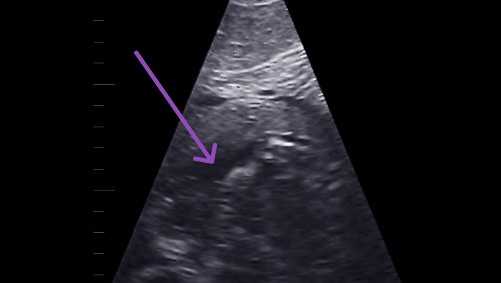

The zoo said the pregnancy was first detected through urine hormones and confirmed through voluntary transabdominal ultrasound.